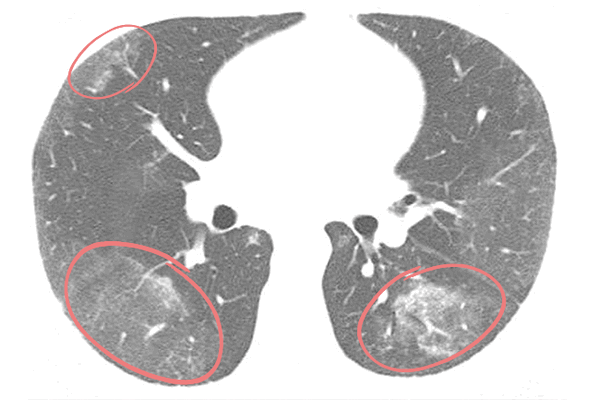

Оценивая данные КТ легких, врач-рентгенолог дифференцирует заболевания по специфической картине «матовых стекол»: их количеству, локализации, наличию других признаков, по которым возможно определить причину патологических изменений ткани легких. Например, для двусторонней вирусной пневмонии характерно наличие «матовых стекол», расположенных периферически в нижних и задних отделах легких. В более поздней стадии наблюдается консолидация очагов инфильтрации с утолщением перегородок альвеол.

Для пневмонии, вызванной коронавирусом COVID-19, характерно периферическое расположение очагов поражения под плеврой. Наиболее уязвимы билатеральные нижние доли и задние отделы легких. Отмечается тенденция к консолидации «матовых стекол» и утолщению перегородок альвеол, иногда — признаки фиброза легких.

Тяжелым формам коронавирусной пневмонии сопутствует острый респираторный дистресс-синдром. ОРДС — это обширное двухстороннее воспаление, при котором наблюдается множество инфильтратов и отек легких. На томограммах фрагментарные участки «матового стекла» кортикальной формы присутствуют с двух сторон и имеют вид «лоскутного одеяла».